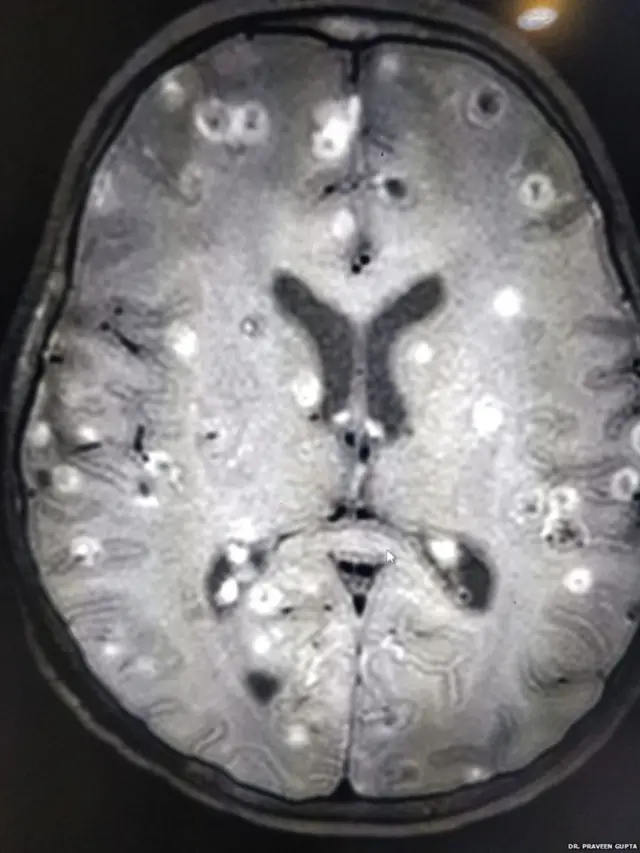

આઠ વર્ષની બાળકીના મગજમાં કૃમિનાં 100થી વધું ઈંડાં જોવાં મળ્યાં. દીકરી માથામાં દુખાવાની ફરિયાદ રોજ શા માટે કરતી હતી, તેને વારંવાર વાઈ કેમ આવતી હતી એ તેના માતા-પિતા સમજી શકતાં ન હતાં.

"બાળકીના મગજમાં 100થી વધુ ટેપવર્મ એટલે કે કૃમિના ઈંડાં હતાં, જે નાનાં-નાનાં ક્લૉટના સ્વરૂપમાં જોવાં મળ્યાં હતાં."

એ બાળકીને ડૉ. પ્રવીણ ગુપ્તા પાસે લાવવામાં આવી ત્યારે તેનું સિટી સ્કેન કરવામાં આવ્યું હતું. તેમાં જાણવા મળ્યું હતું કે બાળકી ન્યૂરોસિસ્ટિસેરસોસિસથી પીડાઈ રહી છે.

ડૉ. પ્રવીણ ગુપ્તાએ કહ્યું હતું, "બાળકીને હોસ્પિટલે લાવવામાં આવી ત્યારે એ બેભાન હાલતમાં હતી. સિટી સ્કેનમાં તેના દિમાગમાં સફેદ ડાધ જોવા મળ્યાં હતાં.”

"એ ડાઘ બીજું કંઈ નહીં, કૃમિનાં ઈંડા હતાં અને પણ એક-બે નહીં, 100થી વધું હતાં."

બાળકીને ડૉ. પ્રવીણ ગુપ્તા પાસે લાવવામાં આવી ત્યારે તેના દિમાગ પરનું પ્રેશર ઘણું વધી ચૂક્યું હતું. ઈંડાંનું દિમાગ પર એટલું દબાણ હતું કે બાળકીનું મગજ કામ કરતું બંધ થઈ ગયું હતું.

ડૉ. ગુપ્તાના જણાવ્યા મુજબ, બાળકીના દિમાગમાં ઈંડાંની સંખ્યા સતત વધી રહી હતી. એ ઈંડા સોજા અને વાઈનું કારણ બનતાં હતાં.